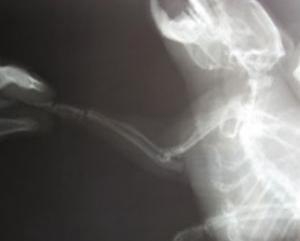

На перше місце британці помістили відкриття рентгенівського випромінювання і винахід медичних приладів, які використовують його . Цей варіант підтримали 10 тисяч опитаних. Друге місце зайняло відкриття пеніциліну. На третє місце жителі Великобританії помістили визначення структури ДНК. Далі йдуть створення корабля "Аполлон-10" і балістичної ракети "Фау-2", винахід паровоза, обчислювальних машин, парового двигуна, масового автомобіля і телеграфу. Оригінальний список винаходів був складений співробітниками Музею науки.